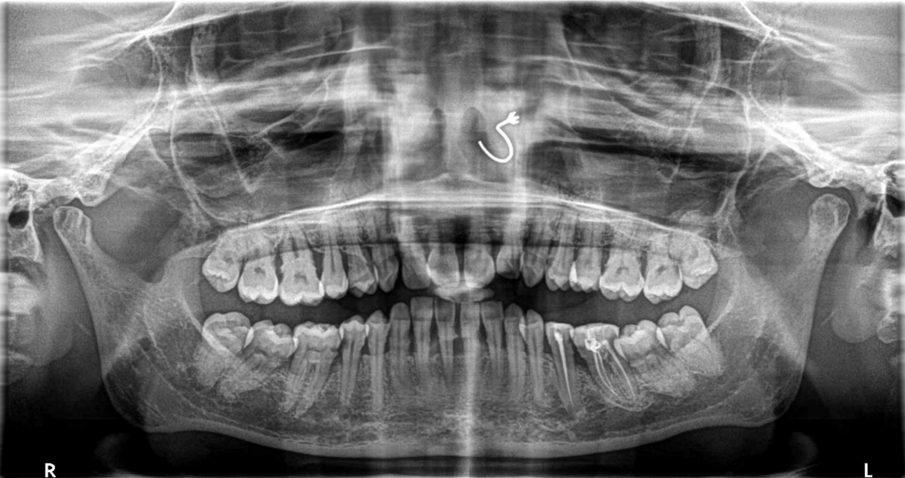

The critical stage of treatment planning is the determination of a tooth’s prognosis. There are several ways of helping with this decision-making – some quite elaborate and expansive taking into consideration both patient factors like willingness and finances and clinical factors like pocket depth, etc.1 Unfortunately, though we make decisions based on bone loss, pocket depth, mobility, etc., —the truth is that the same teeth with the same conditions existing in different patients will have a different prognosis based on hygiene, maintenance, follow-up, masticatory loads, and a certain degree of unpredictability brought in by a wide range of variables that exist at any given time in a patient’s mouth. A clinician’s expertise with regard to both diagnosis and treatment will also determine the success of either treatment. Therefore, following a set flowchart to decide the fate of a tooth is not enough—a clinician needs to bring acumen, experience, something close to intuition, and knowledge of that particular patient to the table. Consolidate all the data and then decide the best course of action.

Even so-called hopeless teeth have been preserved successfully with adequate periodontal treatment followed by strict supportive periodontal treatment (SPT).2,3 Patients with treated aggressive periodontitis have also shown survival of teeth as long as 15 years after treatment.4 This means that patients with seemingly hopeless dentition too could be given the option of holding on to their teeth. They need to be informed that it will just come with a caveat that they must take responsibility for their condition and strictly follow the dentist’s treatment plan and maintenance protocol. At such a time we need to refrain from glamorising the alternative option of an implant—falsely presenting it in a way that suggests that it does not need as much care or that it would last forever. It holds to reason if presented in such a manner 100% of patients who could afford implants, would opt for implants. As soon as an implant is presented as an option it creates a bias in treatment planning as well.5 An implant success rate of 98% and above is misleading as that only refers to its survival in the mouth and not a peri-implant disease, inflammation, or bone loss that afflicts a great number of those surviving implants.6 Therefore, it becomes imperative to present dental implants in a responsible ethical manner—explaining the benefits but also the fact that it is not a fill-it-and-forget-it-situation.

For all patients who opt to save their teeth—the maintenance phase is not just important for the survival of teeth—it is also to ensure no deterioration to a point where it would compromise or jeopardize future implant treatment. We have often in our experience found patients stable for four to six years with regular SPT and suddenly be lost to recall until they turn up ten years later where we are left with no bone to place implants in a conventional manner then resorting to extreme bone augmentation or zygomatic and pterygoid implants. Hence the delicate balance of when saving teeth versus extracting and implants needs to be revisited regularly in each patient to ensure that maintenance of the teeth is not risking the loss of residual bone.